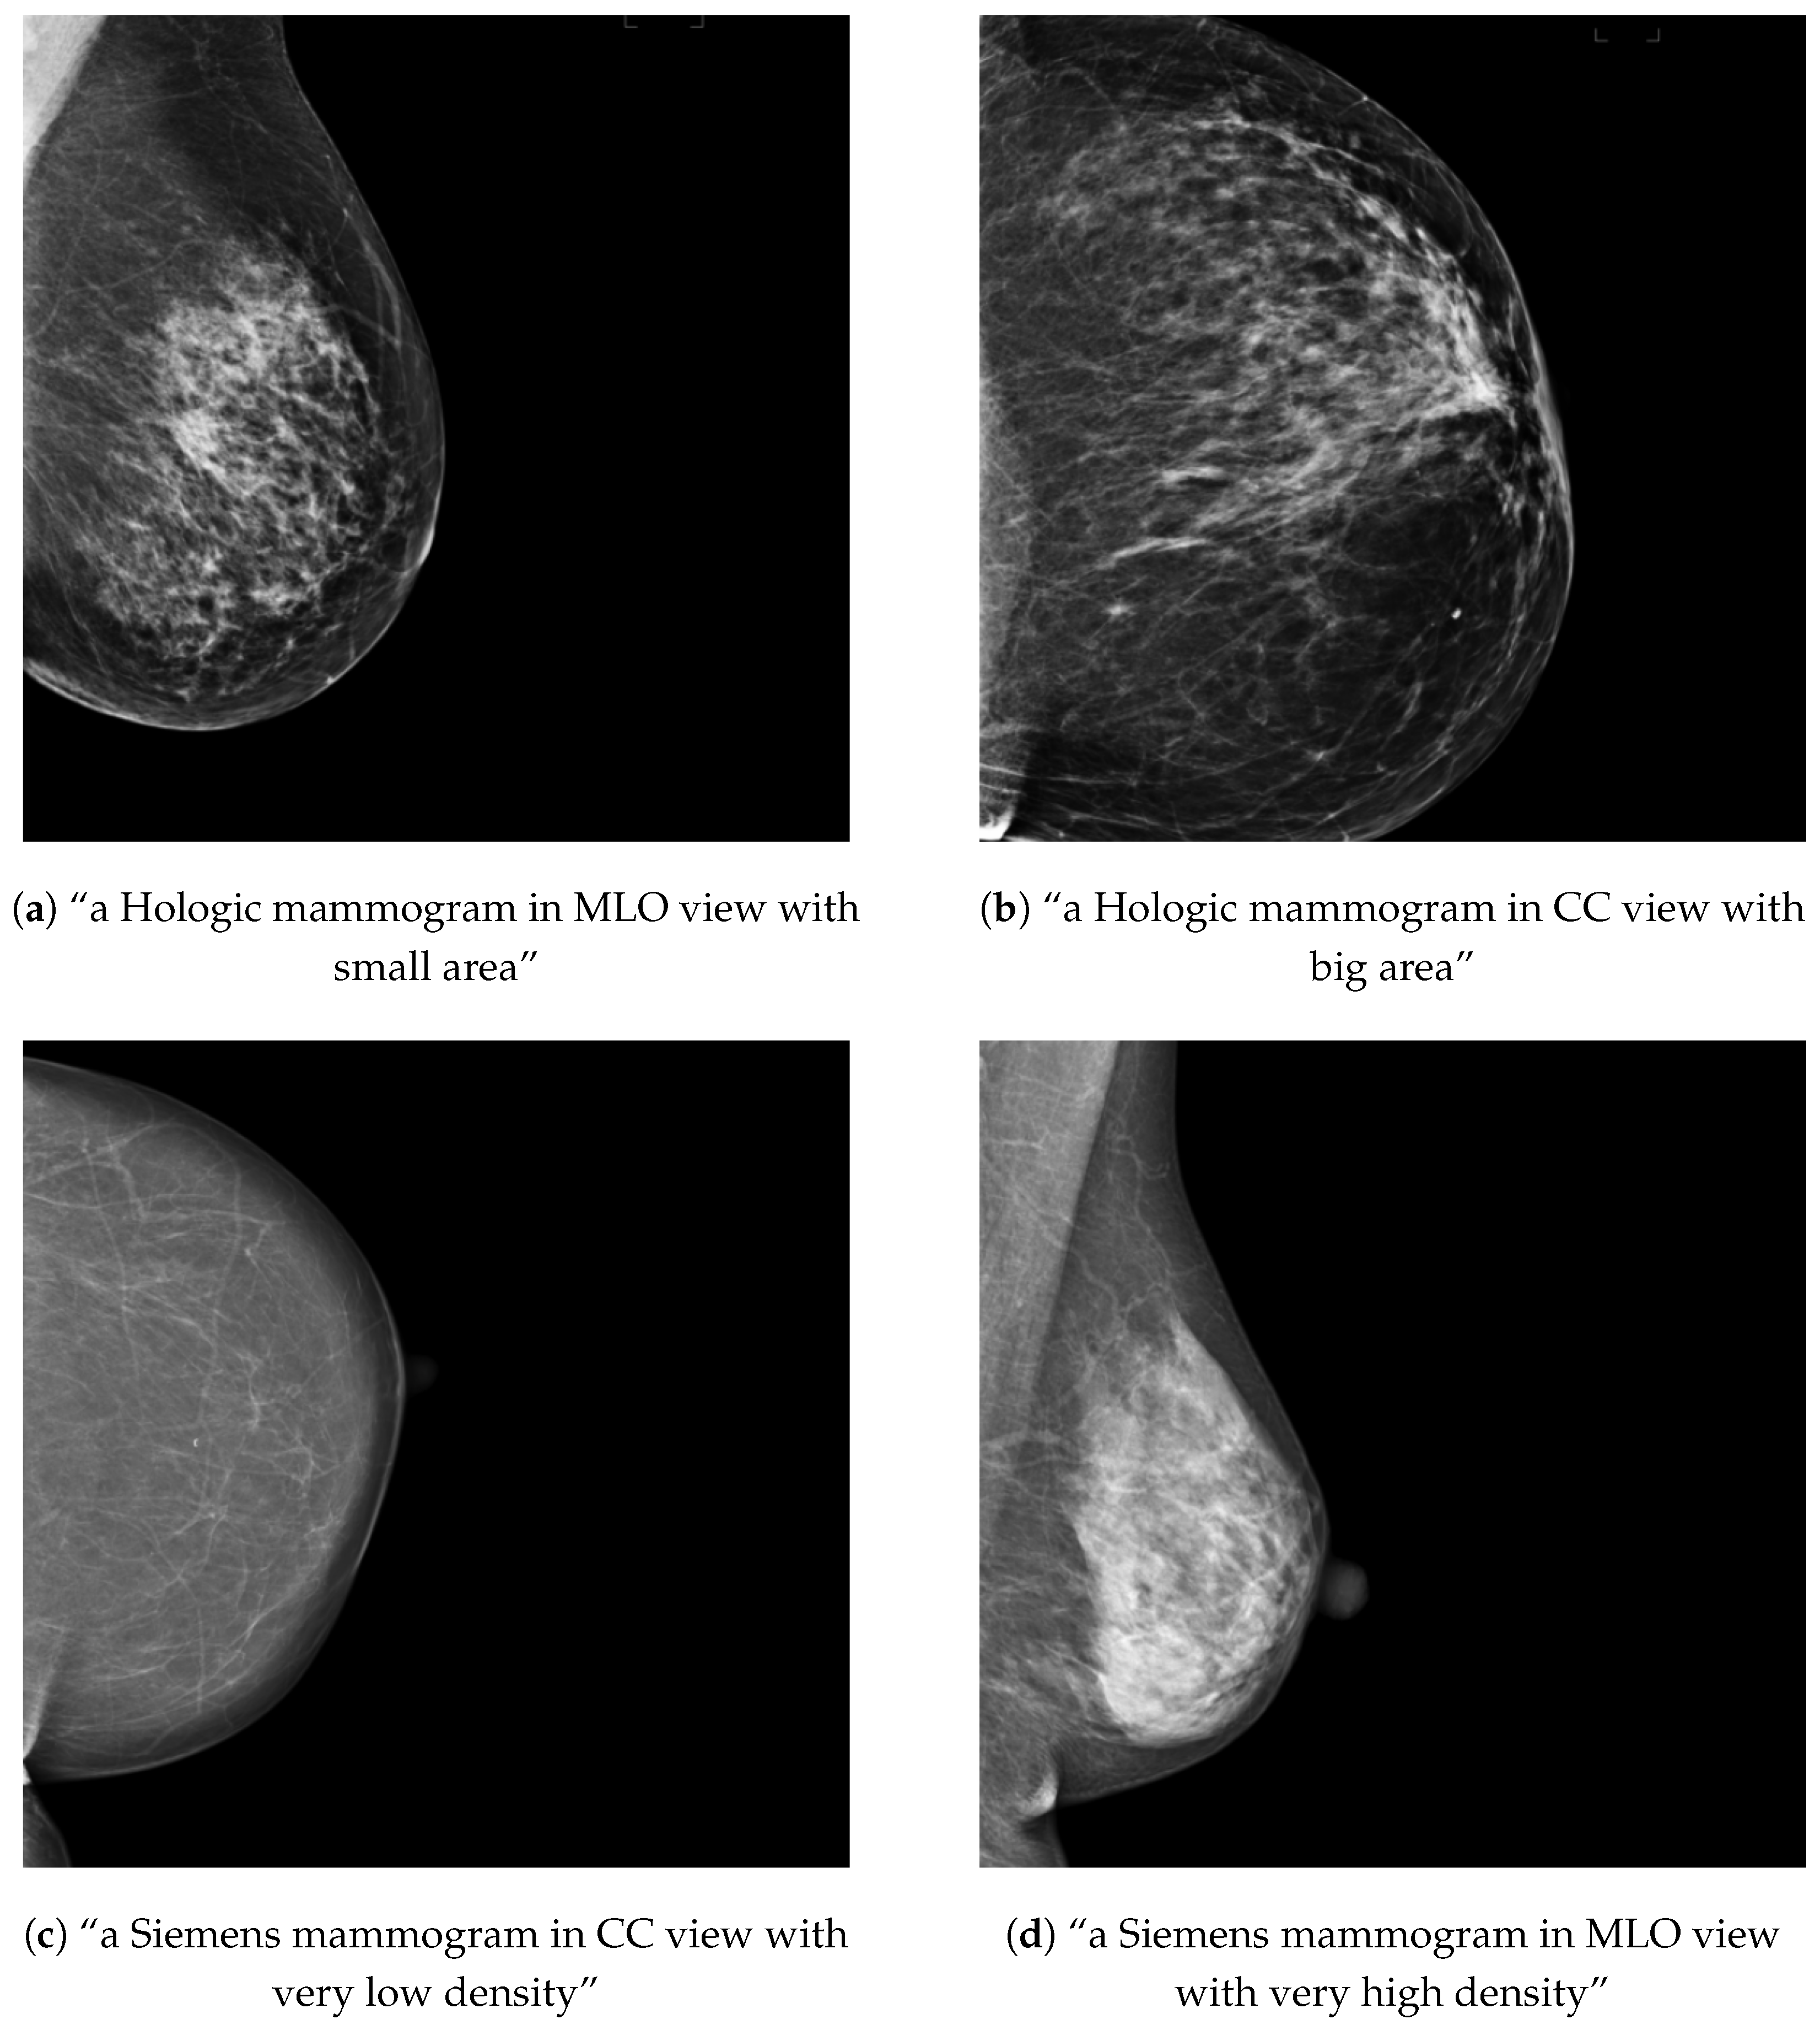

Figure 3.

Examples of training mammograms (real) and their respective text prompts for OMI-H (a,b) and VinDr (c,d).

For each healthy mammogram, a text prompt description was created and saved along with the image ID in a JSON file. In the case of the OMI-H dataset, we created a prompt with the image view and breast area size information. To compute the breast area size, we first obtained a breast mask using the intensity information of the image and then applied a threshold to separate background and breast tissue. Later, the ratio of pixels in the mask compared with the total image was computed and criteria for three different breast area sizes was defined, as shown in Table 2. For the VinDr dataset, the breast density information was included instead of the breast area for the prompt description. Breast density was available in BI-RADS scale, so we needed to transform this information into a semantically meaningful text following the criteria in Table 2, based on the BI-RADS breast density descriptions [27]. Examples of the text–image training samples can be found in Figure 3.

Training examples of the two separate conditional models using prompt text are shown in Figure 13 for the OMI-H dataset and Figure 14 for the VinDr dataset. We observe that the fine-tuning technique allows the generation of meaningful images from epoch one. For the Hologic example, we can observe that, as the training process increases, the mammogram reduces its shape in accordance to the area described in the prompt text. Moreover, it can be noticed that our models differentiate the overall intensity appearance of mammograms, which is different between Hologic and Siemens systems.